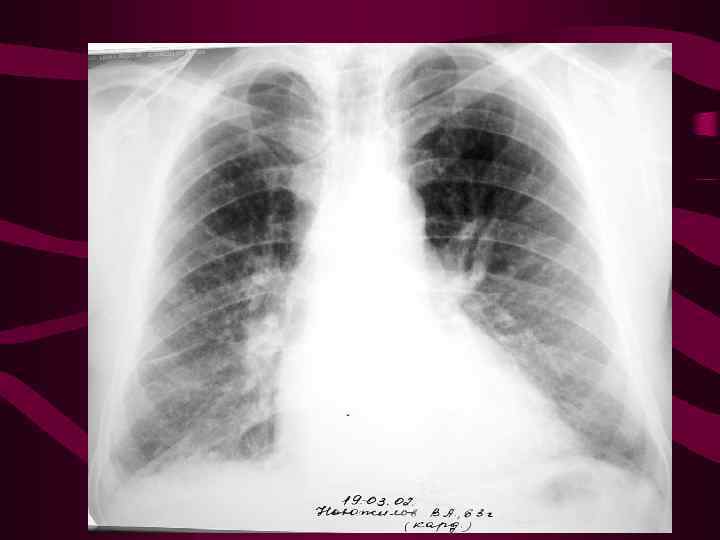

4 - альвеолярный отек легких Изменения соответствуют среднему давлению в левом предсердии свыше 35 мм рт. ст. На фоне венозного застоя с признаками интерстициального отека определяются множетсвенные сливающиеся, разной величины очаговые тени в легких за счет скопления эксудата в альвеолах. Очаговость имеет неравномерную интенсивность и нечеткие очертания, может быть симметричной, двухсторонней, но может быть и односторонней. Нередко выпот в плевральных полостях.

4 - альвеолярный отек легких Изменения соответствуют среднему давлению в левом предсердии свыше 35 мм рт. ст. На фоне венозного застоя с признаками интерстициального отека определяются множетсвенные сливающиеся, разной величины очаговые тени в легких за счет скопления эксудата в альвеолах. Очаговость имеет неравномерную интенсивность и нечеткие очертания, может быть симметричной, двухсторонней, но может быть и односторонней. Нередко выпот в плевральных полостях.